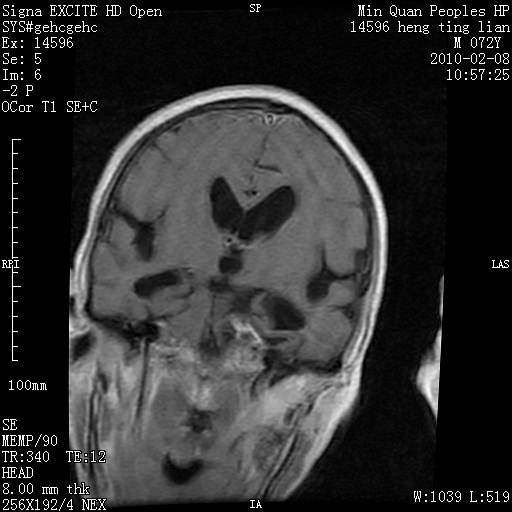

m,72,头疼,头晕两年,伴视力模糊三月,饮食呛咳两天。pe:颈部抵抗,左眼突出,左眼瞳孔约3mm,对光反射消失,双眼失明,伸舌困难,双肺呼吸音粗,心率110次/分,左上肢肌力i级,左下肢屈曲,肌张力高。现有08年2月19mri平扫及10年2月8日mri增强请会诊。ct病灶呈低密度伴散在点、片状等密度区,无明确钙化(无ct片资料可供上传)。[

脑外肿瘤,囊实性,环状不规则强化,内听道扩大,考虑神经源性肿瘤

左侧桥小脑区占位伴梗阻性脑积水----考虑 1神经鞘瘤 2室管膜瘤。

脑外肿瘤,病灶呈匍匐蔓延,表皮样囊肿可能性大。